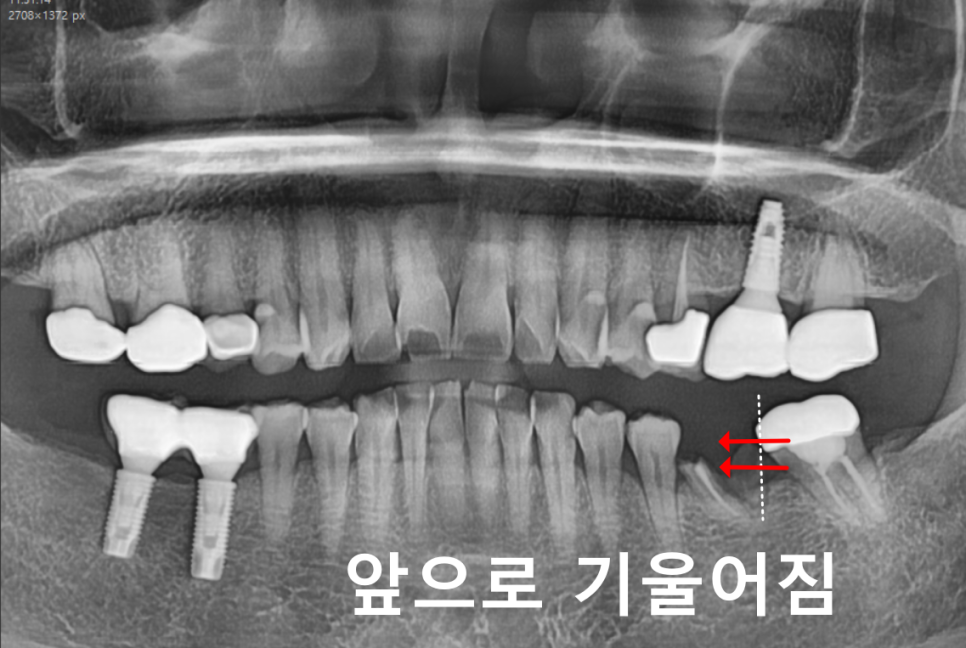

교합이 망가집니다.

고덕동 임플란트

빈 공간이 생기면 양옆 치아들이

그쪽으로 기울기 시작합니다.

241205

위아래 맞물리던 치아도

빈 공간 쪽으로 내려오거나 올라옵니다.

251114

그러면 전체 교합 구조가 무너지면서

턱관절 문제까지 생길 수 있습니다.